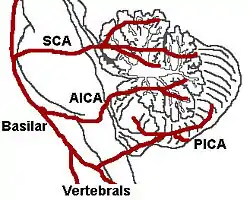

| The three major arteries of the cerebellum: the SCA, AICA, and PICA | |

Cerebellar stroke syndrome is a condition in which the circulation to the cerebellum is impaired due to a lesion of the superior cerebellar artery, anterior inferior cerebellar artery or the posterior inferior cerebellar artery.[1]